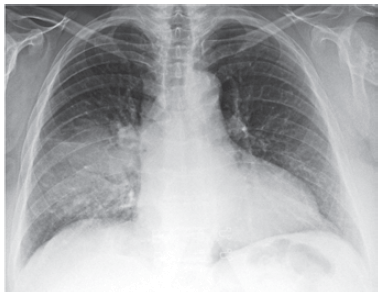

Mulher de 42 anos, sem comorbidades, apresenta quadro de 3 dias de anorexia, prostração, febre e tosse. Não há espirros, rinorreia ou disfonia. Ela nega tabagismo, etilismo e uso de drogas. Exame físico: temperatura: 38,5 ºC; frequência respiratória: 18 ipm; pressão arterial: 120 x 80; frequência cardíaca: 95 bpm; oximetria de pulso com saturação de 97%; ausculta pulmonar com crepitações em metade de hemitórax direito. Teste rápido de COVID e influenza são negativos. A radiografia de tórax realizada é mostrada a seguir.